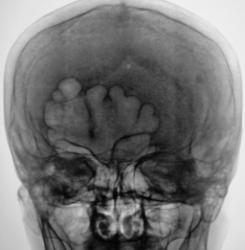

Представлены, на диске, такие изображения черепа.

Представлены, на диске, такие изображения черепа. Что посоветуете уважаемые коллеги?

Уважаемый  Валентин Львович, я так понимаю Вас смущает ячейки лобной пазухи? В данном случае надо обратить внимание на толщину костей крыши черепа, а следовательно и на турецкое седло, следует проконсультироваться у эндокринолога с дальнейшим проведением МР-исследования гипофиза.

По моему у Ясиновской когда -то читал, что гиперпневматизация пазух - косвенный признак эндокринной патологии, а так ничего настораживающего.

Структура затылочной кости не совсем обычная...похоже на "пробойниковые отверствия"...касаемо лобных пазух - такой "фасон", мне кажется это природа, и мало вероятно, что ендокринология...

Кости свода толстоваты, пазухи крупные. Турецкое седло не изменено. По-моему, стоит беспокоиться, только если есть эндокринные нарушения.

Файзуллин, если мне не изменяет память, частенько, гиперпневматизацию пазух связывал с опухолевым ростом. Но в данном случае, по всей видимости, вариант или аномалия развития лобной пазухи.